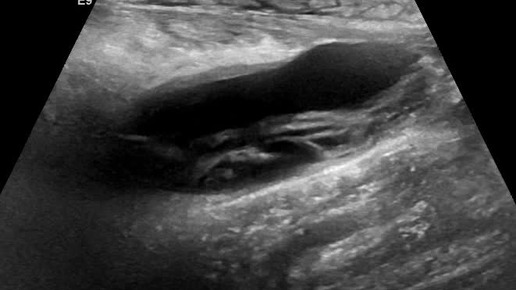

Видео к статье "Разрыв икроножной мышцы".https://dzen.ru/a/Z8AwLJ00NlZOFhsx

Ультразвуковые находки от врача УЗД Зорина Я.П.